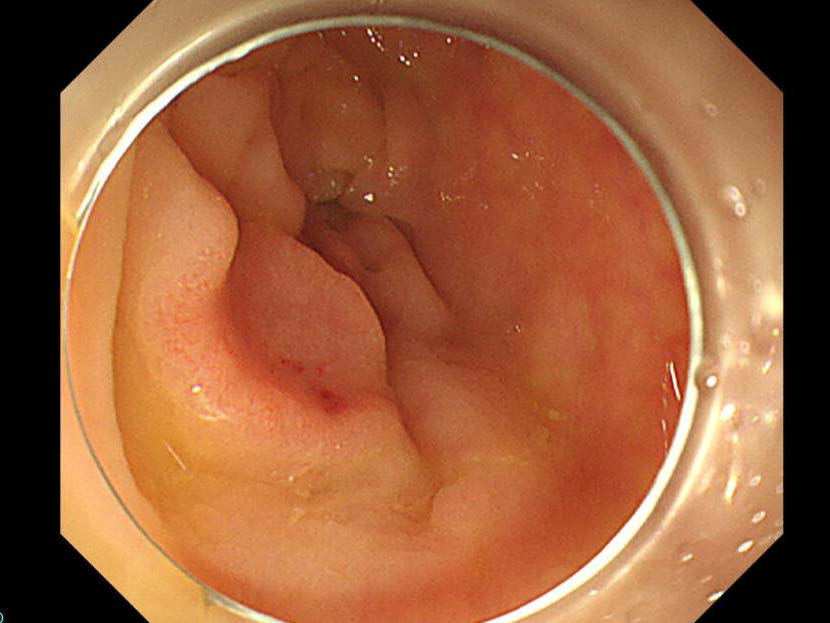

消化管Mapping~大腸~ 2021.10.27

消化管Mapping~大腸~

消化管Mapping